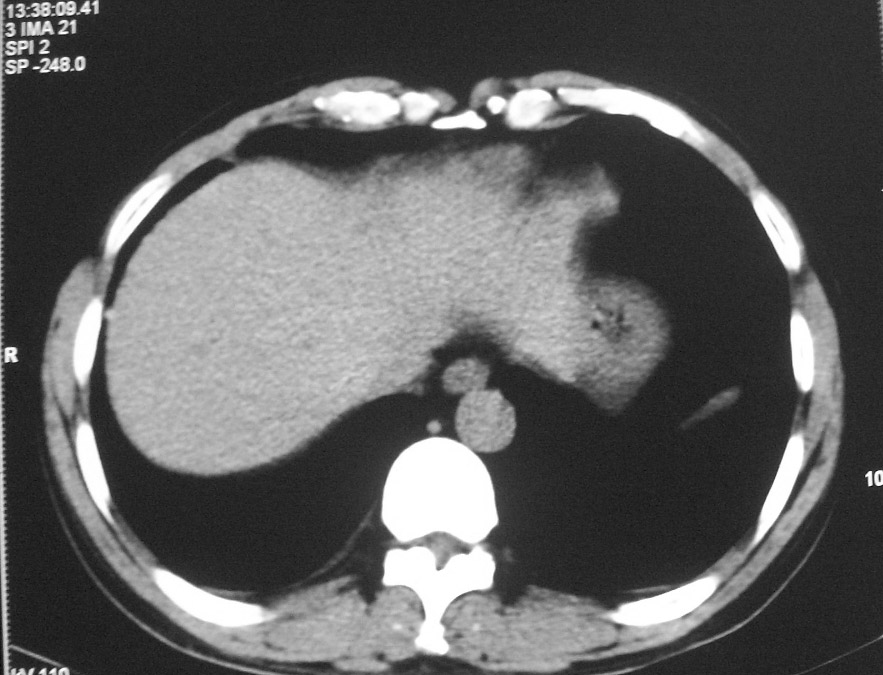

标题: CT5485:[原创]肺部占位请讨论

右肺上叶中央型肺癌并上叶肺不张、纵隔淋巴结肿大

右上叶支气管后壁明显增厚,支持右肺上叶中央型肺癌伴右上叶肺不张、纵隔淋巴结肿大。

右肺上叶中央型肺癌并上叶肺不张

右上叶支气管开口变窄,纵隔见肿大的淋巴结。支持右上叶中心型肺癌并右上叶不张纵隔淋巴结肿大。

右肺上叶中央型肺癌并上叶肺不张、纵隔淋巴结肿大.右侧少量胸腔积液。

右上肺中心型肺癌并肺不张,纵膈淋巴结肿大。右侧少量胸腔积液。

右肺上叶不张,考虑中央型肺癌。右侧胸膜肥厚

右肺上叶中央型肺癌并阻塞性炎症、阻塞性肺不张……